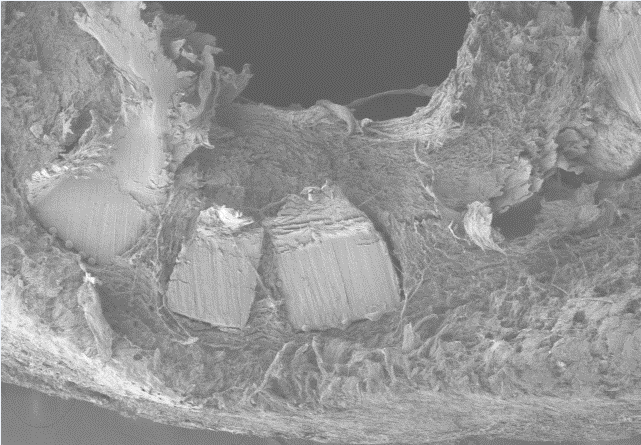

扫描电镜样本准备方法及要求:

动物组织样本

① 1-3min内取样,组织块不超过3mm2,用PBS轻轻漂洗将样本表面的血污,毛发等去掉,将需要扫描的面做好标记(如在对面进行剪角处理)。

② 取材时一定注意避免镊子挤压等机械损伤,刀片要锋利避免挫伤组织。尤其是注意保护扫描面。

③ 组织取下后立即投入电镜固定液内室温固定2h,再转移至4°保存,4°冰袋运输,在保存和运输过程中固定液切勿冷冻结冰。